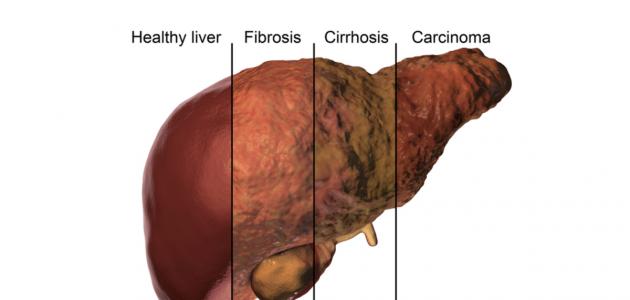

إنّ تليف الكبد (بالإنجليزية: Liver fibrosis) وتشمّع الكبد (بالإنجليزية: Liver cirrhosis) من الأمراض التي تُصيب الكبد وتؤثر في قدرته على أداء وظائفه، إذ يحدث تليف الكبد نتيجة تشكّل نسيج ندبي في الكبد استجابةً للإصابة بأمراض الكبد المزمنة؛ مثل: الإصابة بالتهاب الكبد الوبائي “ب” أو”ج”، أو مرض الكبد الدهني غير الكحولي (بالإنجليزية: Fatty liver disease) سواء الكحولي أم غير الكحولي، وهذا بحدّ ذاته يؤثر في قدرة الكبد على العمل بكفاءة، ومع مرور الوقت وتزايد الندبات، قد يؤدي ذلك إلى تطوّر حالة تشمّع الكبد،[١][٢] ولكن عادةً ما يستغرق الأمر سنوات حتى تصل الحالة إلى هذه المرحلة كما ويمكن أن يُساعد العلاج في إبطاء تطورها، وتجدر الإشارة إلى أنّ تليف وتشمّع الكبد ليسا مرضيين بحدّ ذاتهما بل هما ناتجين عن عواملٍ أدت إلى تلف الكبد،[٣][٤] وبمجرد تطور الحالة للتشمّع فإنّ ذلك يزيد من احتمالية حدوث بعض المضاعفات الخطيرة، مثل: ارتفاع ضغط الدم البابي (بالإنجليزية: Portal Hypertension)، أو فشل الكبد (بالإنجليزية: Liver failure)، أو سرطان الكبد (بالإنجليزية: Liver cancer).[٣]

يحدث تليّف الكبد نتيجة تعرض الكبد بصورةٍ مستمرةٍ أو متكررةٍ للضرر والتلف الذي يؤثر فيه، فكلمة تليّف تُشير إلى تندُّب الكبد بسبب تعرضه لعمليات التئام غير منتظمة ومتكررة، ومن الجدير ذكره أنّ الكبد يقوم عادةً بإصلاح نفسه وتكوين خلايا كبديّة جديدة بصورةٍ طبيعية، وعليه فإنّ تكرار الإصابة أو استمرارها لمدةٍ طويلة سيكون مصحوبًا بمحاولة خلايا الكبد إصلاح الأضرار باستمرار، وهذه المحاولات قد تتسبّب بتكوين نسيج ندبيّ يحلّ محل خلايا الكبد الطبيعية، ويُشار إلى أنّ هذه الندبات لا تؤدي أيّ وظيفة بل إنّها تؤثر في بُنية الكبد وقد تتداخل مع عملية التدفق الطبيعي للدم من الكبد وإليه، وذلك من شأنه أن يقلل من تدفق الدم لخلايا الكبد، وقد يترتب على ذلك موت الخلايا وتكوّن المزيد من الندبات، والتي بدورها قد تتطور لتكوين التليف، وقد يحدث التليّف بشكلٍ أسرع عندما يكون ناجمًا عن حدوث انسداد في القنوات الصفراويّة (بالإنجليزية: Bile Ducts)، وفي بعض الأحيان يمكن السيطرة على التليّف إذا تمّ تحديد الأسباب وتداركها بالطريقة الصحيحة، أمّا في حال استمر التليّف لفتراتٍ زمنيةٍ طويلةٍ واستمر التليّف وانتشر في الكبد؛ فقد يؤدي ذلك إلى تدمير البنية الداخلية للكبد وتأثّر قدرته التجدّد والقيام بوظائفه الأخرى، ويُعرف التليّف الشديد في هذه الحالة بمصطلح تشمّع الكبد؛ وعليه فإنّ تشمّع الكبد ما هو إلّا مرحلة متقدمة جداً من التليّف.[٥][٤]